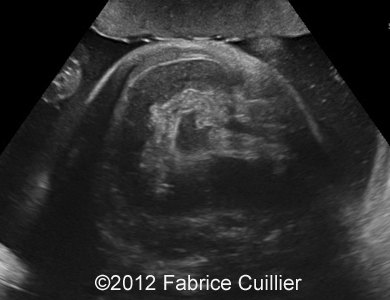

At 28 weeks, ultrasound examination revealed an abnormal fetus, with moderate polyhydramnios, moderate ileal and jejunal dilatation (Image 1) with normal peristalsis. There was no pyelectasy. There were no other dysmorphologic signs of aneuploidy. There was no sign of meconium peritonitis. There was no sign of congenital infection. The maternal serological status did not show any sign of maternal infection (TORCH and Parvovirus B19). Our first hypothesis of diagnosis was congenital chloride or sodium diarrhea. But sodium and chloride level in amniotic fluid were normal (results from first amniocentesis).

Image 1: At 28 weeks and 29 weeks, moderate ileal and jejunal dilatation.